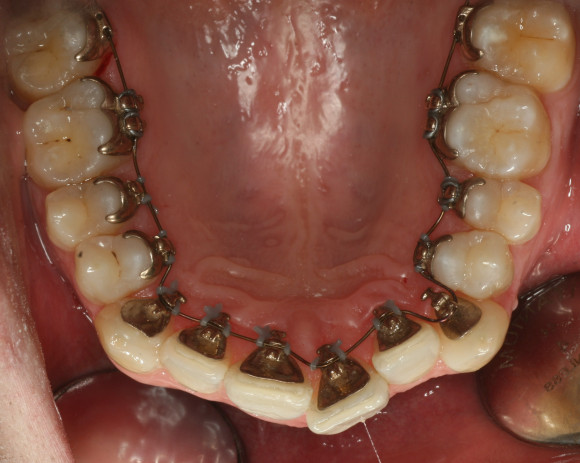

Zahnregulierung mit innen-liegendenBrackets:

Für bestimmte Patienten sind feste Zahnspangen das bessere Therapiemittel. Die Brackets werden individuell für jeden Patienten angefertigt und mit einem spezielle Kleber auf den Zähnen fixiert. Eine Bogensequenz von unterschiedlichen Drahtbögen bringt die Zähne in die gewünschte Position. Von Aussen ist diese Form der Zahnspange nicht sichtbar. Hiermit können nahezu alle Zahnbewegungen durchgeführt werden.